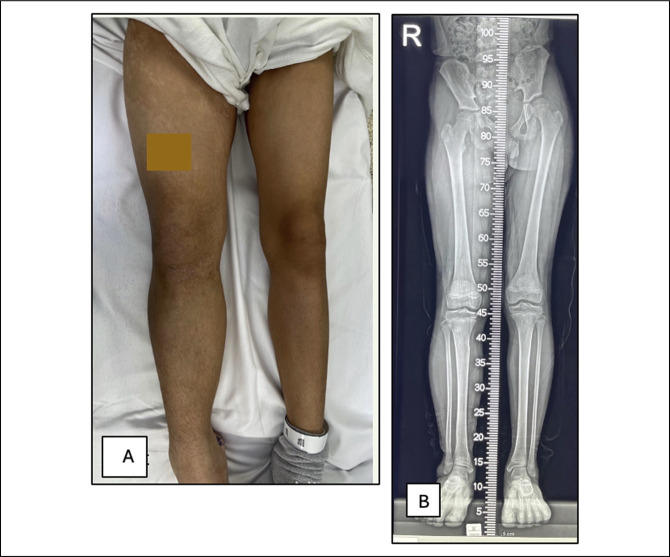

这个报告描述了一个15岁的青春期男孩患有1型神经纤维瘤病,在他的身体的右半部分有区域体细胞嵌合。其独特的临床特征是下肢广泛性半肥厚,伴长骨进行性生长迟缓,导致肢体缩短。患者成功地接受了肢体延长手术。据我们所知,这是第一篇报道1型神经纤维瘤病患者肢体延长手术的文章,该患者因36%的基因缺失而在同一肢体上出现两种主要的相反生长现象。

This presentation describes a 15-year-old adolescent boy with neurofibromatosis type 1 with regional somatic mosaicism in the right half of his body. The unique clinical features are highlighted by generalized hemihypertrophy of the lower extremity in association with progressive growth retardation of long bones, which results in limb shortening. The patient successfully underwent limb lengthening. To our knowledge, this is the first neurofibromatosis type 1 article to report of a limb-lengthening procedure in a patient with two major and opposite growth phenomena on the same limb caused by a 36% gene deletion.